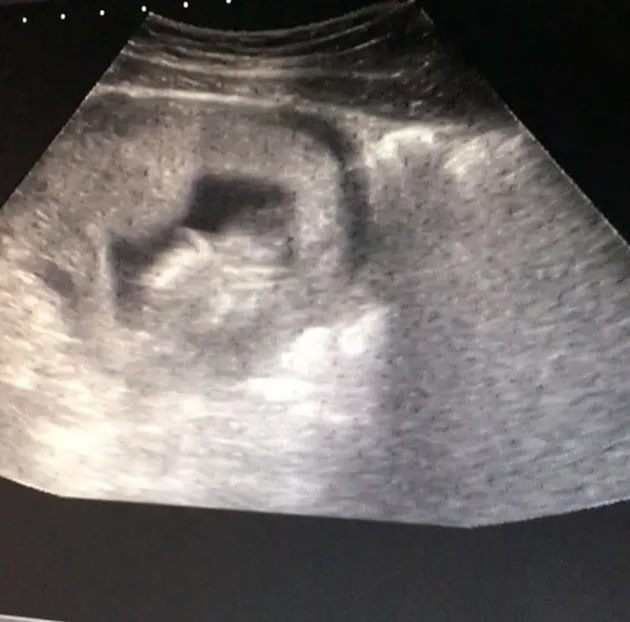

Kabar bahagia datang dari artis cantik Melody Prima. Setelah menikah dengan pria pujaannya, Tommy Bagus, kini bintang sinetron Anak Menteng ini sekarang sudah berbadan dua alias hamil. Perut Melody pun kini sudah mulai terlihat buncit, tapi ia tetap cantik banget. Lihat deh foto-fotonya!

Diketahui, Melody kini tengah berbadan dua. Pemain FTV ini pun sudah beberapa kali memeriksakan kandungannya.